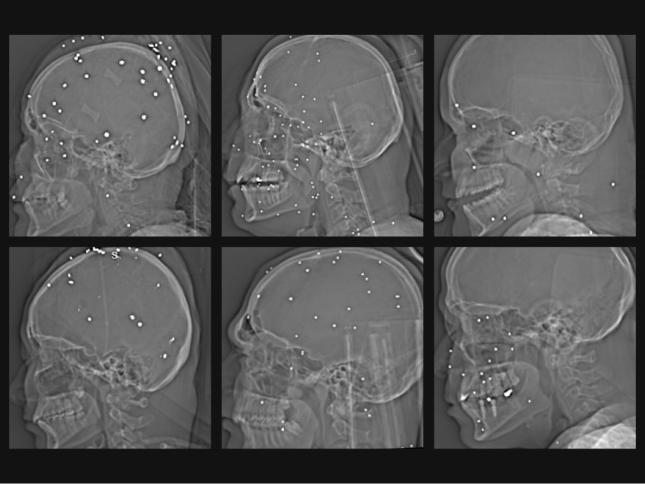

سیاسی و اجتماعی گزارش گاردین از عکسهای رادیولوژی مجروحان قیام ملی؛ «به اعضای حیاتی بدن شلیک کردهاند» بررسی تصاویر یک بیمارستان که مجروحان قیام ملی به آن مراجعه کردهاند نشان میدهد که آسیب شدید به صورت، سینه و اندام تناسلی ناشی از گلولههای ساچمهای فلزی و کالیبر بالا بوده است شلیک کور حکومت سرکوب به کودکان؛ بچههایی که ۱۵ سالگی را ندیدند بازداشت برادر برای تسلیم او؛ روایت فریب و قتل عباس رشیدی در سمیرم اصفهان چهلم جاویدنامان؛ مادرانی که تهمینهوار سوگ جوانانشان را به حماسه تبدیل کردند